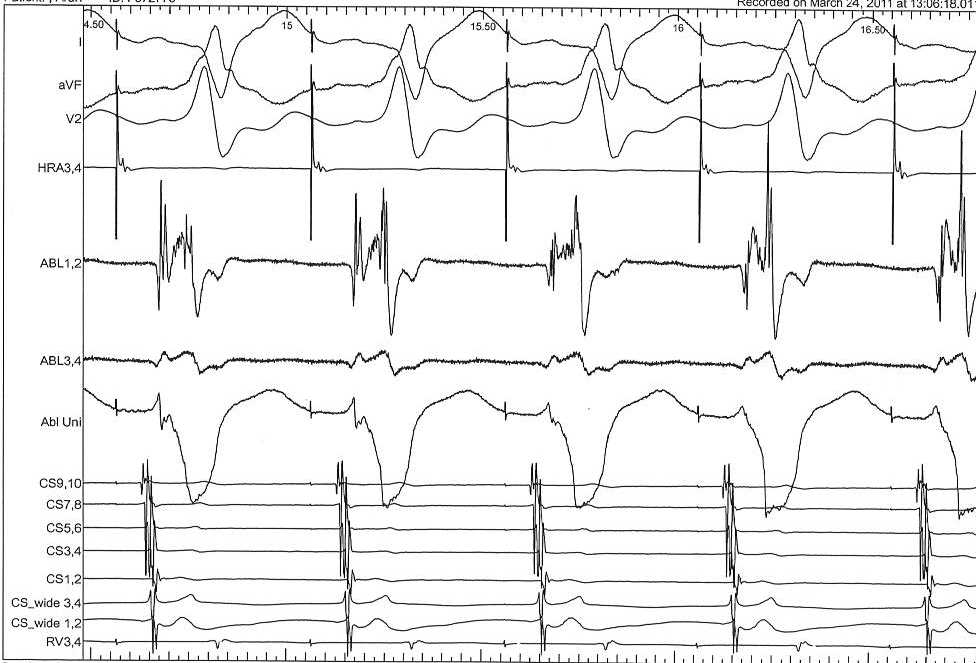

Septal pathways - Ablate during tachycardia

asap_ablation_tachy.jpg